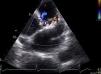

Further echocardiographic assessment in parasternal view documented dilatation of the pulmonary artery trunk (34 mm) and normal-sized right chambers. Doppler echocardiography identified continuous laminar flow, mainly in diastole, peak velocity 0.1 m/s (Figure 2), corresponding to the site of coronary fistula drainage. Areas of turbulent flow were seen along the course of the anterior descending artery, corresponding to branching of the fistula at this point (Figure 3). Pulmonary artery pressure was estimated at 28 mmHg. No other congenital defects were detected.

Transthoracic echocardiogram, parasternal short-axis view. Left: color Doppler showing laminar flow draining into the proximal portion of the pulmonary artery trunk (yellow arrow), as well as slight pulmonary regurgitation; right: continuous Doppler revealing the flow to be systolic-diastolic (mainly diastolic), with peak velocity of 1.0 m/s.